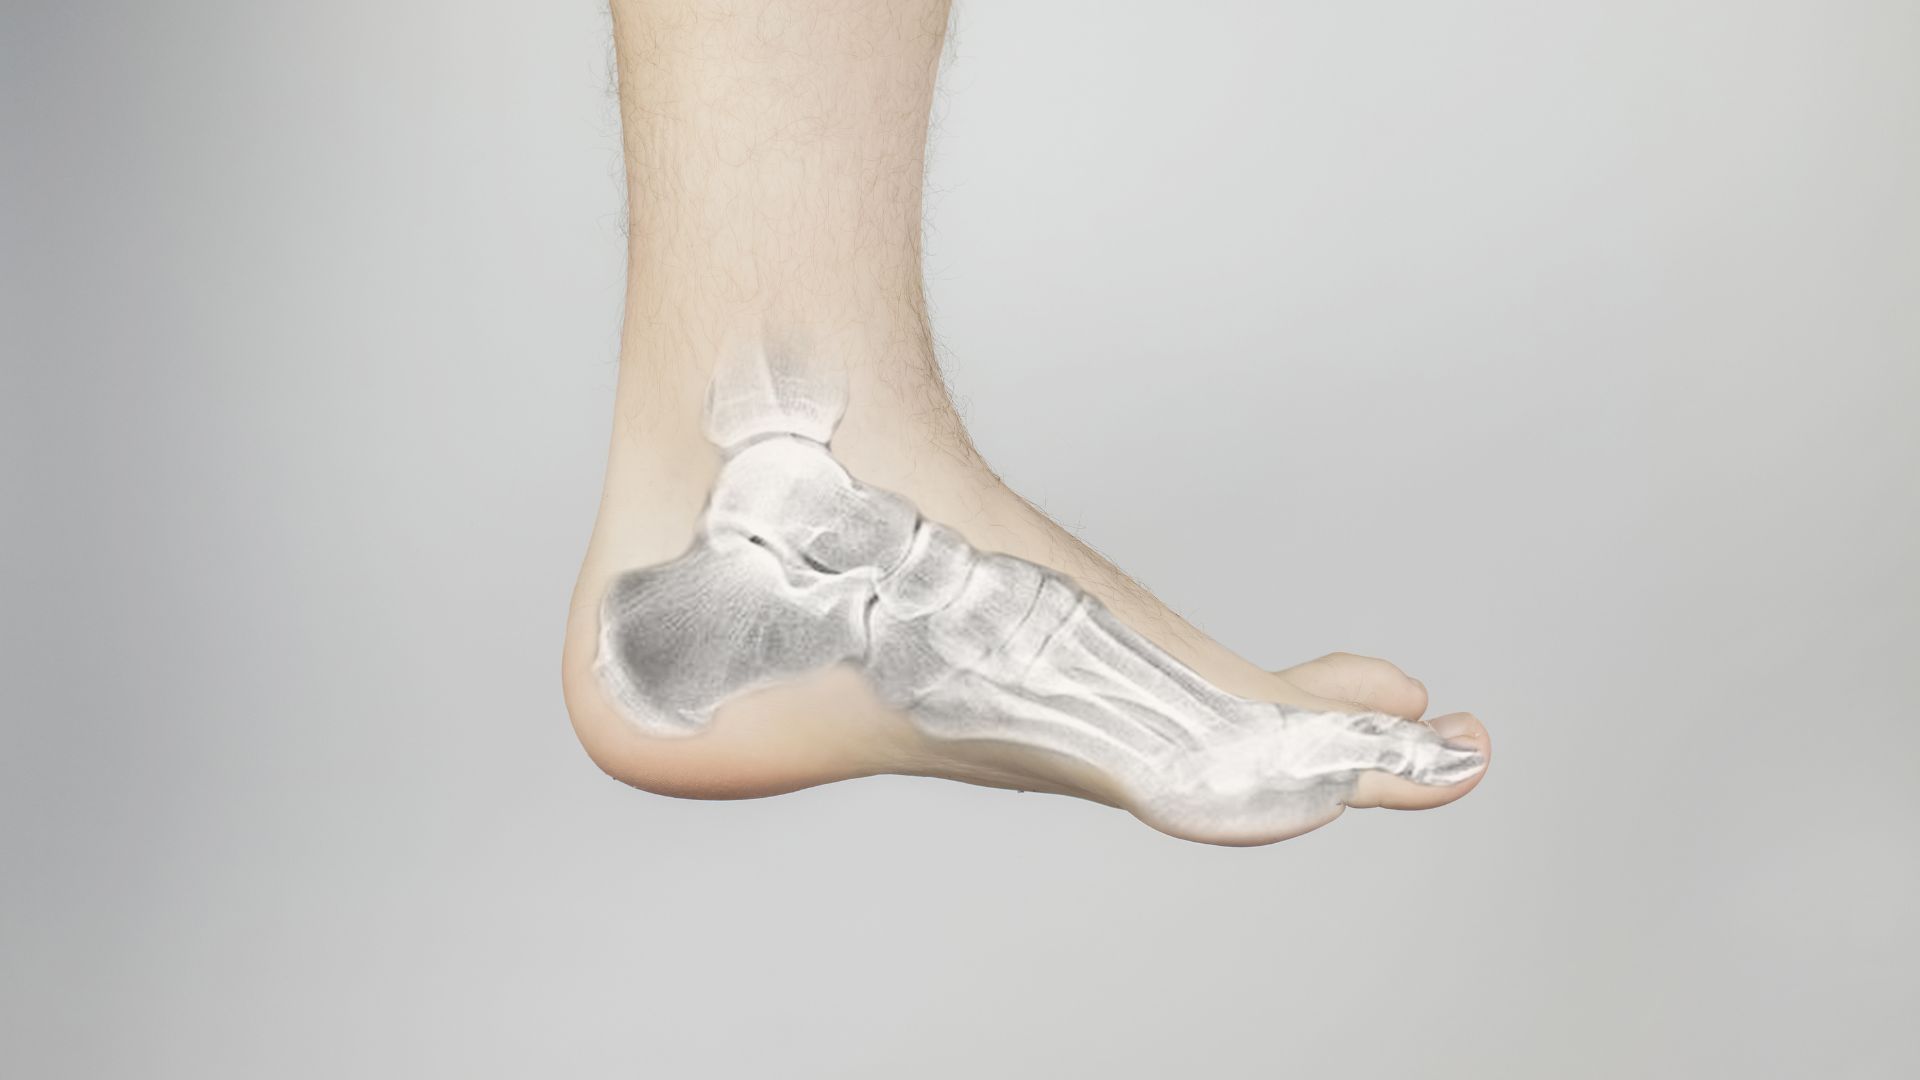

Bàn chân là một cấu trúc giải phẫu phức tạp với 26 xương cùng nhiều khớp và hệ thống dây chằng liên kết chặt chẽ. Khi xuất hiện các biểu hiện như đau, sưng, hạn chế cử động hoặc biến dạng, các phương tiện chẩn đoán hình ảnh trong đó có X-quang xương bàn chân đóng vai trò quan trọng trong việc hỗ trợ đánh giá và định hướng xử trí phù hợp.

Do bàn chân chịu lực thường xuyên và có cấu trúc giải phẫu phức tạp, nhiều tổn thương không thể nhận biết đầy đủ chỉ bằng quan sát hoặc sờ nắn. Trong đánh giá các bệnh lý và chấn thương vùng bàn chân, việc kết hợp giữa thăm khám lâm sàng và chẩn đoán hình ảnh giúp nâng cao độ chính xác trong xác định nguyên nhân. Dưới đây là một số ý nghĩa của X-quang xương bàn chân trong chẩn đoán như: